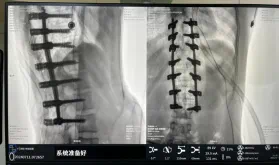

圖為置釘后

此次在充分保證患者安全和手術(shù)效果的前提下使用機(jī)器人輔助下手術(shù)的成功實(shí)施,大大降低了高難度手術(shù)的風(fēng)險(xiǎn),并進(jìn)一步減輕了患者手術(shù)創(chuàng)傷、縮短了康復(fù)時(shí)間。這也標(biāo)志著南方醫(yī)院贛州醫(yī)院脊柱外科治療個(gè)性化、精準(zhǔn)化、智能化水平進(jìn)一步提升。